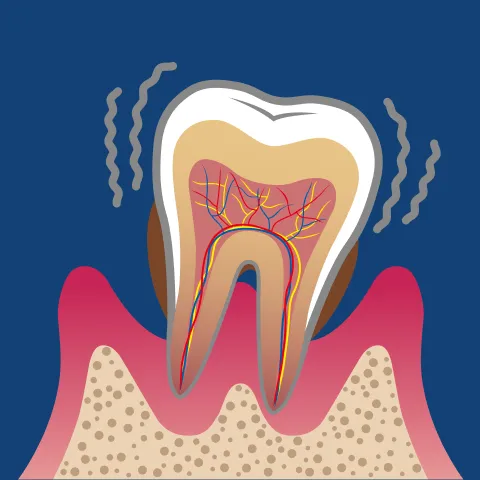

歯周病とは、歯を支える「歯ぐき」や「歯槽骨(しそうこつ)」といった土台の組織が、細菌によって徐々に破壊されていく病気です。

原因となるのは、歯と歯ぐきの境目に付着する「歯垢(プラーク)」という細菌の塊。歯垢の中には、わずか1mgに約10億個もの細菌が潜んでおり、その中に含まれる「歯周病菌」が毒素を放出して歯ぐきに炎症を引き起こします。炎症は時間の経過とともに歯ぐきの奥へ広がり、最終的には歯を支える骨まで溶かしてしまいます。

初期の段階ではほとんど痛みがないため、気づかないうちに病状が進行していくのが特徴です。このため、歯周病は“サイレントディズィーズ(静かな病気)”と呼ばれています。

歯ぐきの赤みや腫れ、歯みがき時の出血といった軽い症状を放置していると、歯がぐらついたり、やがて抜け落ちてしまうこともあります。むし歯がなくても歯を失う原因の多くを占めているのが、この歯周病です。

歯をしっかりと支えているのは、目に見えない部分にある「歯槽骨」という骨です。

歯周病が進行すると、歯周病菌が放出する毒素や炎症性物質がこの骨にまで影響を与え、少しずつ吸収・破壊していきます。骨が減少するにつれて歯の根が露出し、支えを失った歯は動きやすくなります。患者さんの中には「歯が浮いたような感じがする」「前歯のすき間が広がってきた」といった変化を感じる方も少なくありません。

歯槽骨が溶けていくスピードには個人差がありますが、数年単位で進行することが多いです。

放置すれば、炎症がさらに広がり、最終的に歯が自然に抜け落ちてしまうこともあります。実際、日本人が歯を失う原因の第1位はむし歯ではなく歯周病です。